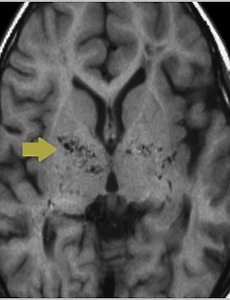

모야모야병 증상 그리고 완치 모야모야병 증상 그리고 완치 사람의 뇌는 좌우 내경동맥과 좌우의 추골동맥 총 4개의 혈관으로 영양을 받고 이들의 4개 혈관은 뇌저부에서 서로 연결되어 윌리스서클을 형성하고 있습니다. 모야모야병 이란 윌리스동맥륜폐색증이라고도 불리며 모야모야라는 이름에서 알 수 있듯이 일본인에게 많이 발생했고 그래서 일본인이 발견한 병입니다. 그럼 도대체 무슨 병인지부터 한번 확인해 보도록 하겠습니다. 뇌 양쯕의 내경동맥 말초부분이 점점 좁아져서 마침내 막히게 되고 그 대신 가느다랗고 흐릿하면서 연기가 올라오는 듯한 모습의 혈관이 뇌에 영양을 공급하게 되는 질환입니다. 뇌혈관조영 영상으로 좁은 혈관이 모여있는 것이 마치 담배연기처럼 모락모락 올라오는 듯한 느낌이라서 일본어로 그런 느낌을 주는 단어인 모야모야병 이라 칭해지게.. 2020. 1. 2.